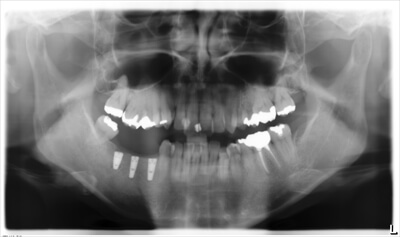

⑦インプラントの治療後のレントゲン写真です。

正確な位置に埋入されています。